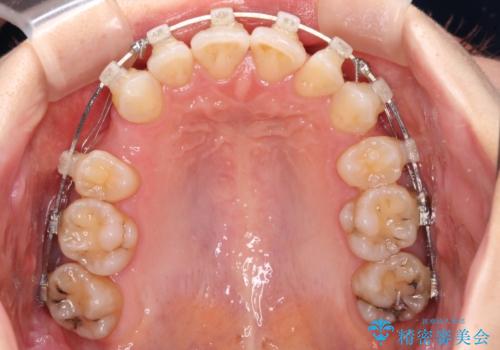

- クリアブラケット

- 八重歯や前歯のデコボコを気にして来院された患者様です。

骨格的な左右差と、歯列から外れている歯が上下で左右非対称になっていることから、上下正中が歯1本分ずれている状態でした。

八重歯の改善と、上下の正中位置を極力合わせていくことを目的として、上下左右の第一小臼歯4本を抜歯し、ワイヤー装置にて矯正治療を行うこととしました。

アンカースクリューを用いて正中位置を調整したことで、上下の正中位置をほぼ一致させることができました。

移動量が多かったため、治療期間は長くなりましたが、大変満足のいく仕上がりとなりました。